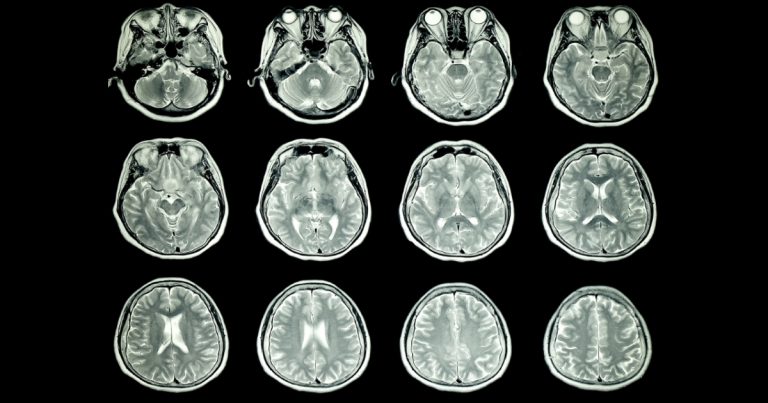

Studie Stanfordské univerzity se zabývá novým postupem pro léčbu depresí. Ten používá transkraniální magnetismus a ukázal se jako neobyčejně úspěšný.

Metoda staví na již dobře známé a schválené léčbě pomocí stimulace zvané iTBS (intermittent theta-burst stimulation). Během tohoto procesu jsou do konkrétní části mozku cíleny magnetické pulsy. Nicméně tento zákrok je třeba provádět každý den po dobu šesti týdnů, léčba tedy trvá dlouho a výsledky se velmi liší případ od případu. Tým ze Stanfordu chtěl tuto metodu vylepšit a rozhodl se pulsy cílit mnohem přesněji podle konkrétních potřeb pacienta.

Zároveň došlo k navýšení počtu pulsů v jednotlivé „dávce“. Dochází tak k mnohem kratší léčbě, která zahrnuje 10 desetiminutových sezení s přestávkou v délce 50 minut. Tohle se děje po dobu 5 dní. Celkem 29 pacientů bylo rozděleno na dvě skupiny, kdy jedna dostávala přesně tyto pulsy (SNT), druhá placebo. Po pouhých 5 dnech léčení splňovalo 79 % pacientů, kteří obdrželi SNT, kritéria pro remisi, a tedy absenci deprese jako diagnózy.